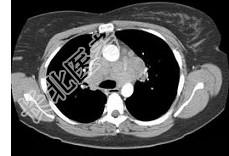

- 单项选择题女,33岁, 咳嗽,乏力, 低热,皮肤有结节, 结合CT图像,最可能的诊断是 ( )

D、结节病